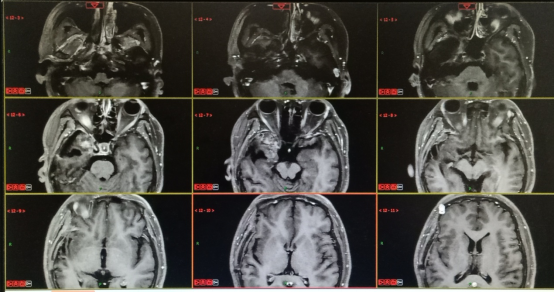

2020.12.08三门峡市中心医院:右侧颞叶胶质瘤术后改变,病变范围较前增大,新见脑桥、右侧额叶强化,考虑肿瘤复发可能。